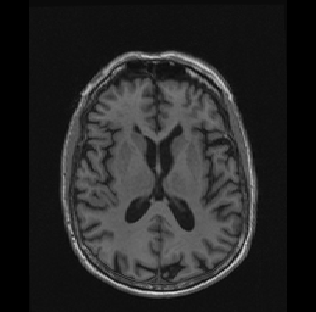

Neuroimaging

The collection and analysis of neuroimaging data, most notably magnetic resonance imaging (MRI), has become a widely used technique in the biomedical sciences over the past twenty years or so. Functional MRI (fMRI), as its name implies, is used to study brain function in an effort to identify neural correlates of certain behaviors, as well as to study the causes, symptoms, and treatments of mental illness such as schizophrenia. It’s generally done by observing the blood-oxygenation-level-dependent (BOLD) signal over time, since this signal is thought to be a good proxy for neuronal activity. Over the past decade, there has been an explosion of interest within the statistics community in fMRI data analysis, resulting in many interesting methods. However, many challenges still remain. My dissertation research involved Bayesian approaches to large-scale inference on functional MRI data while accounting for spatial dependence. Bayesian modeling for fMRI is an issue that I remain interested in. I also have become interested in the analysis of structural/clinical MRI data. Structural MRI is used in clinical settings to study physical characteristics of the brain; e.g., physical changes associated with diseases such as multiple sclerosis or Alzheimer’s disease. Some statistical challenges here involve appropriate methods for quantifying these physical changes over time, identifying the structures of interest in a diseased brain (e.g., segmentation), and relating these characteristics to clinical endpoints.